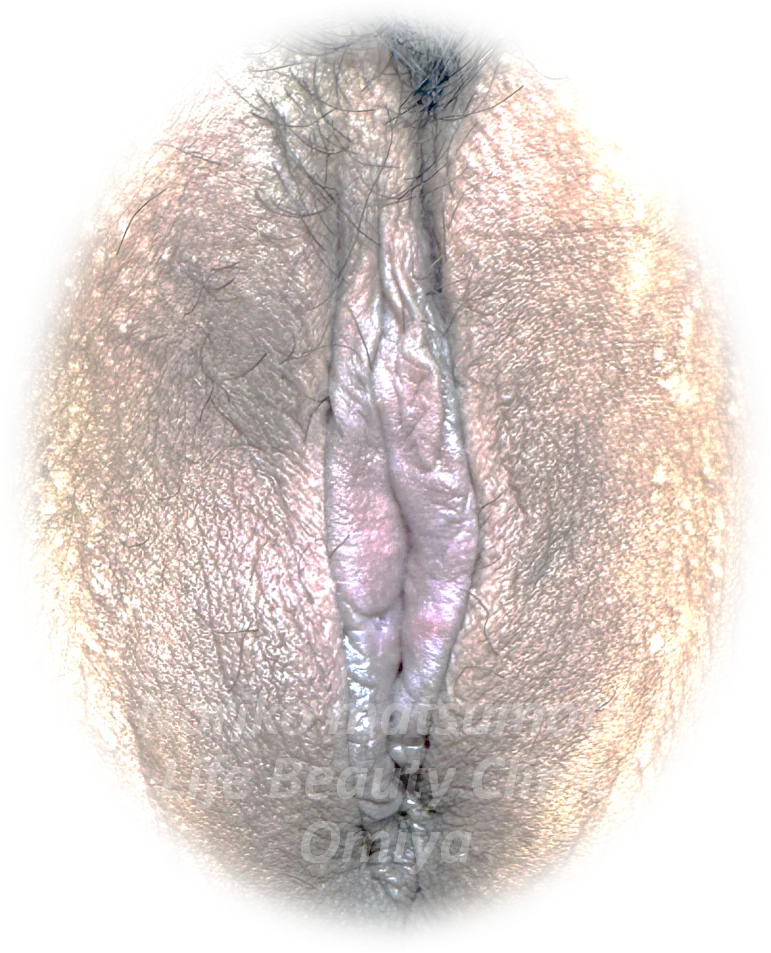

【#1-1】両側副皮+両側小陰唇縮小

術前

術後2ヶ月

| 施術内容 |

両側副皮+両側小陰唇縮小 |

| リスク |

出血、感染、糸の露出、若干の左右差など |

| ダウンタイム |

腫れ・内出血・疼痛 |

| 費用 |

264,000円 |

| 院長の一言 |

大きさ・色でお悩みでした。小陰唇と副皮が陰核包皮と連続している難しいタイプです。肛門側は急峻なカーブで幅がなくなっているのに合わせ、なるべく自然な形になるよう小陰唇をボリュームダウンしました。色味のついた部分もなくなり、トーンアップしました。 |